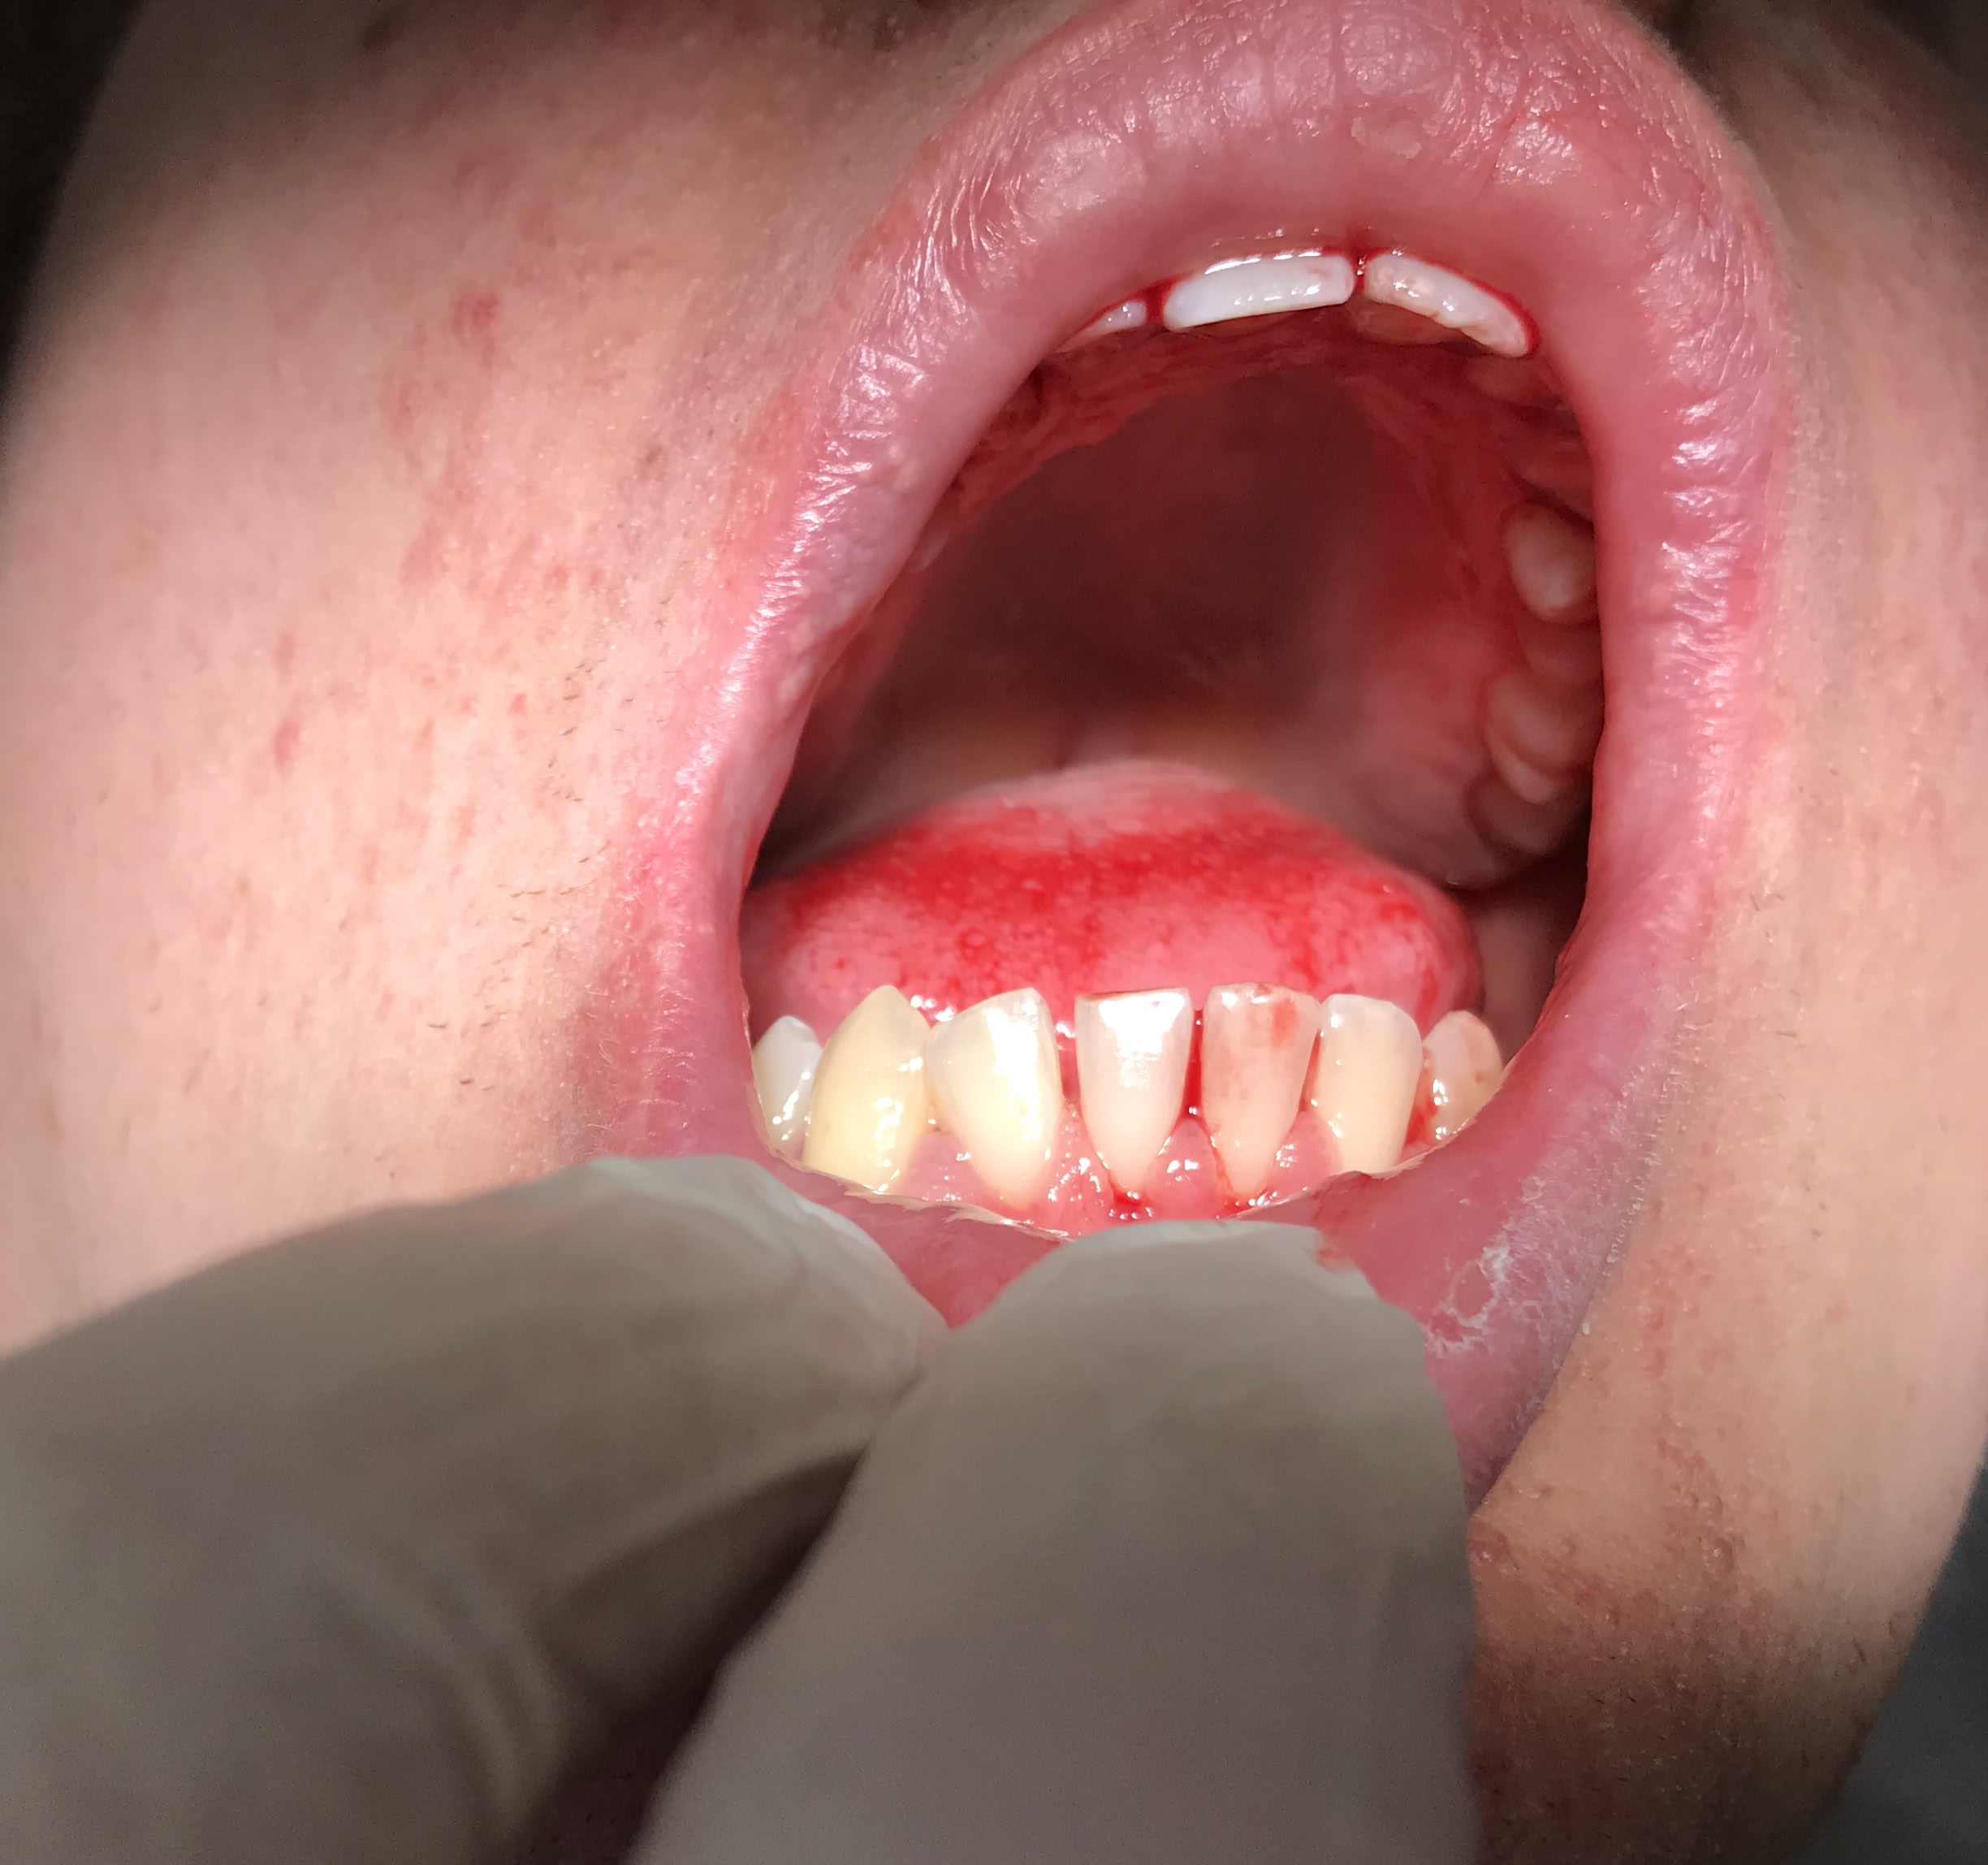

Je suis un patient de 30 ans , et je fais de l’ épilepsie +++. Je fais des détartrages tous les 3 mois. Mes incisives mandibulaires étaient parfaitement alignées. Et là je me retrouve avec ma 42 disto-versée.

Pourquoi ?

C'est la photo ou il décale sa machoire vers la droite?

- j’ai juste détartré cette fois-ci et pris une photo

- non c’est la photo , il ne décale pas sa mâchoire

Un gros kyste entre 43 et 42?

Une dent surnuméraire?

C’est pgc qui a trouvé. T’as gagné une PPA à selles disjointes comme récompense ;))

Pour la petite histoire, il est venu au cabinet en m’expliquant qu’il avait fait une crise d’ épilepsie dans sa piscine et que depuis son incisive avait bougé. Il était persuadé que c’etait suite à un choc dans sa piscine .

Question :

Je vais lui enlever ça, la dent va t elle se repositionner normalement par elle même ensuite ? Ou faut il la repositionner avec une chaînette ou autre ?

Kyste parodontal latéral

D’ailleurs dans cet article ils racontent que ça a une croissance très lente. C’est faux il y a 3 mois il n’avait Absolument rien .... à croire que ça croît rapidement

Je suis d’ accord sauf que sa dent était parfaitement droite il y a 3 mois. Ça prouve bien que ça évolue rapidement

Le kyste était peut être là il y a 3 mois . C’est certainement le cas .... sauf que il y a 3 mois les dents étaient alignées. Ce qui prouve que le kyste grossit rapidement